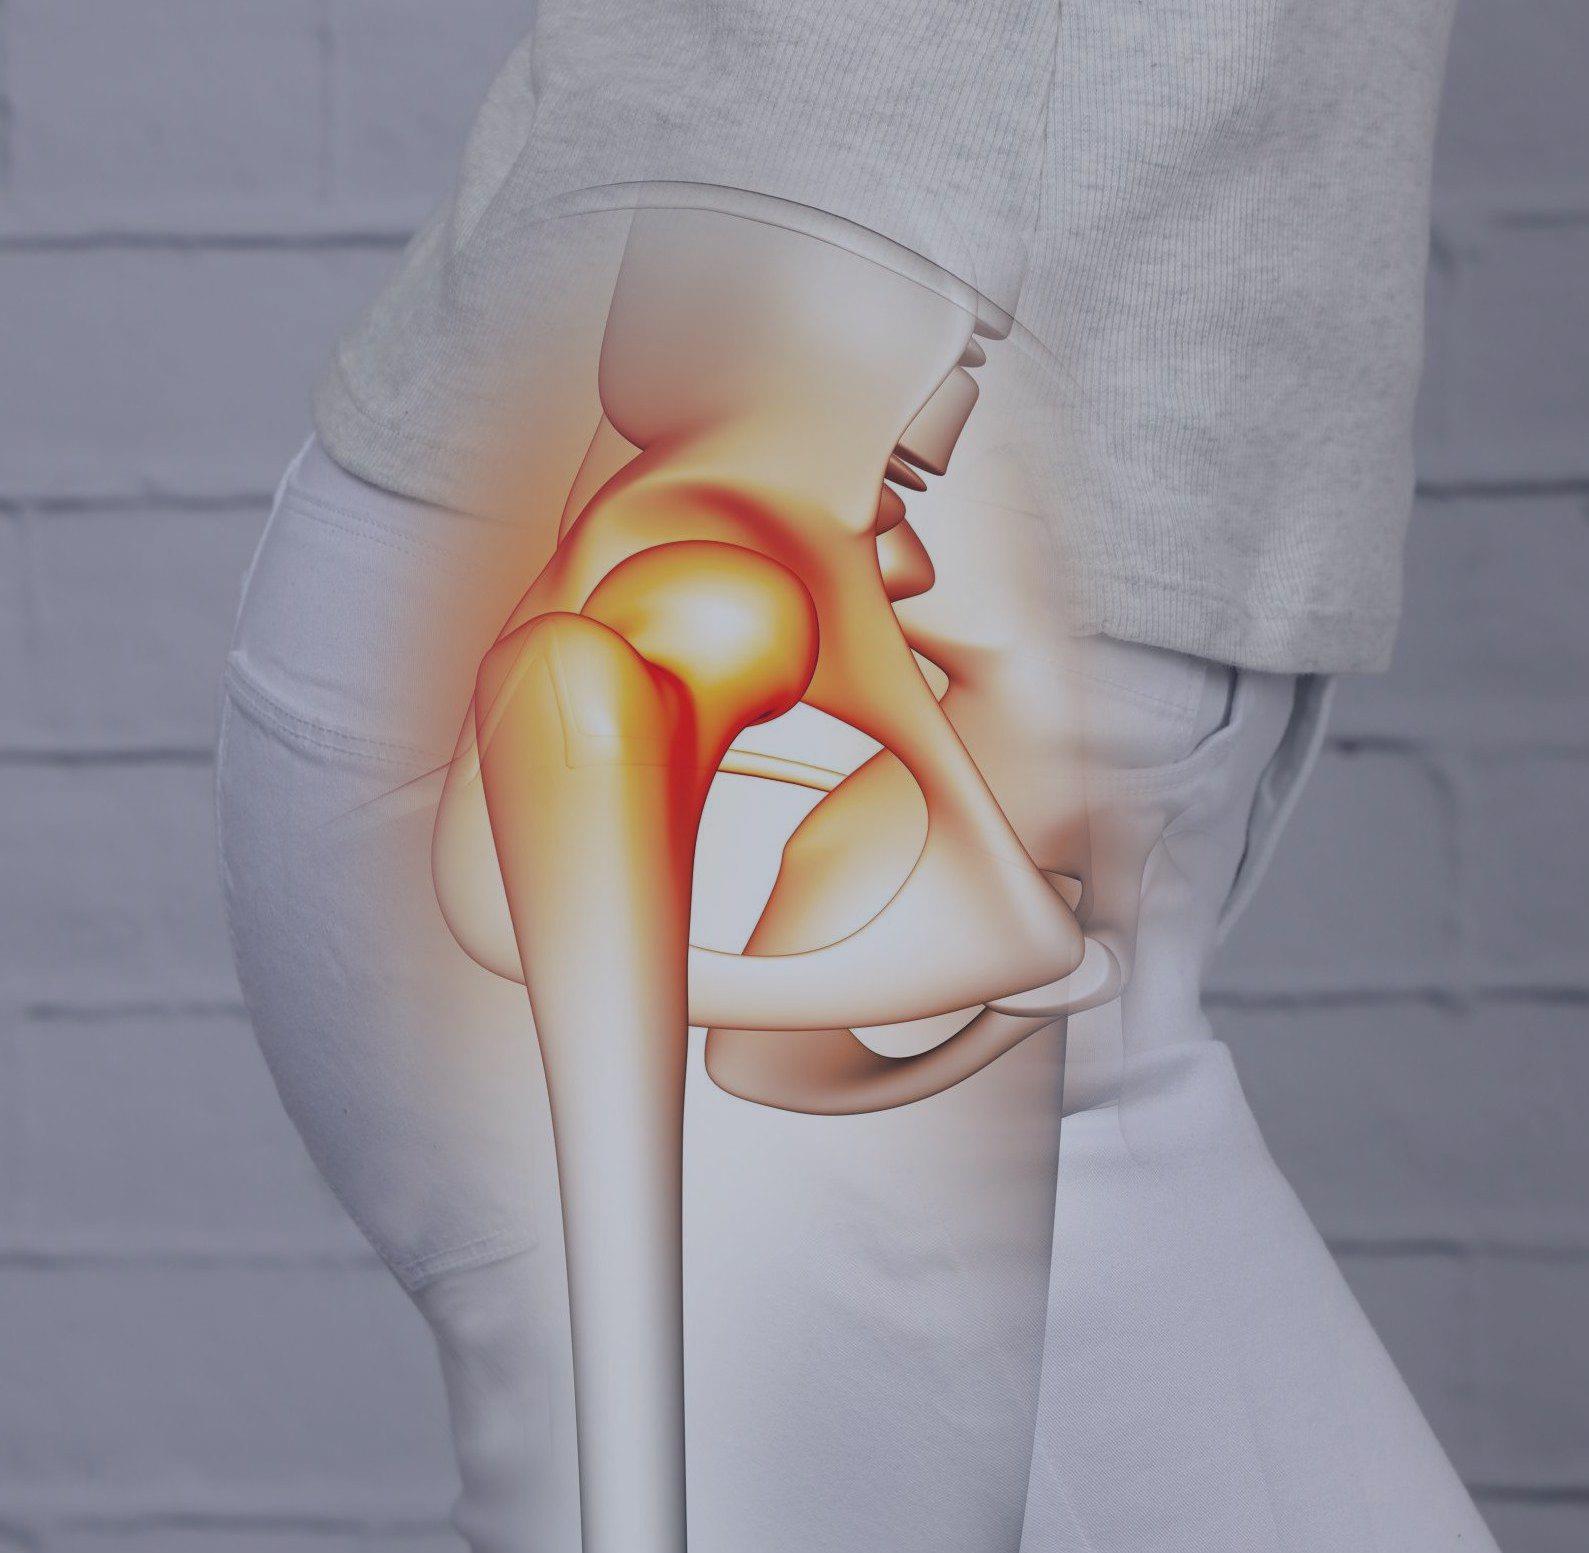

Reemplazo de cadera

Cirugías de Cadera

Dolor persistente, limitación severa del movimiento, inflamación frecuente o falla de tratamientos previos.

Tratamiento:

⦁ Cirugía con prótesis personalizada

⦁ Técnicas quirúrgicas especializadas en rodilla

⦁ Rehabilitación integral tras la cirugía